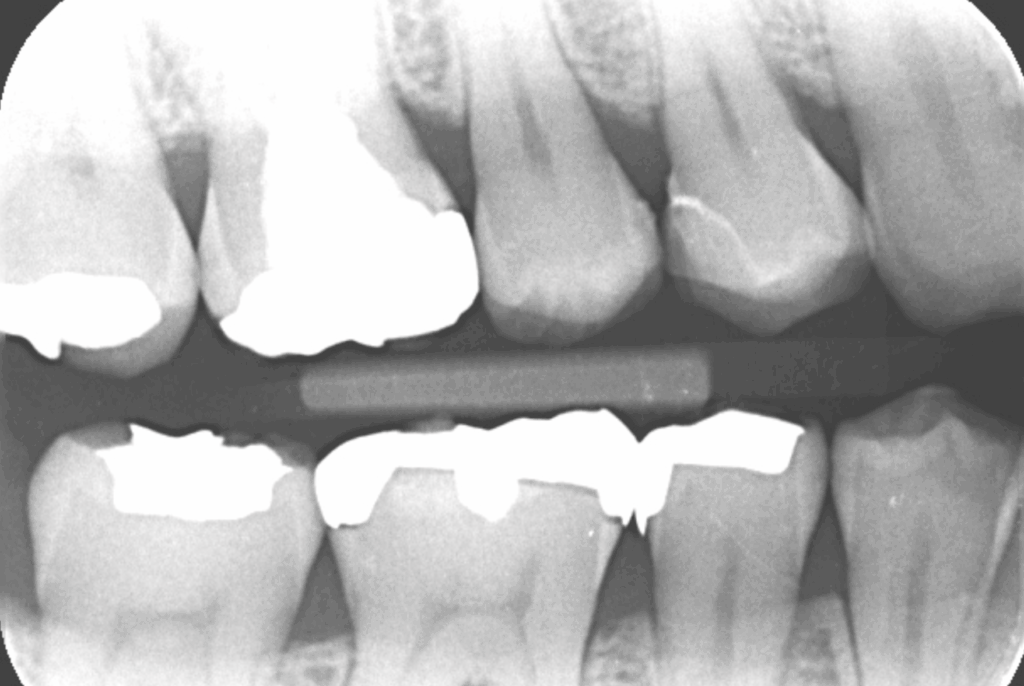

①術前

| 診断 | ①右上4う蝕 ②左上67う蝕 ③左下67う蝕 |

| 処置内容 (または主訴) | ①セレックインレー ②右上6セレックインレー 右上7CR ③セレックインレー |